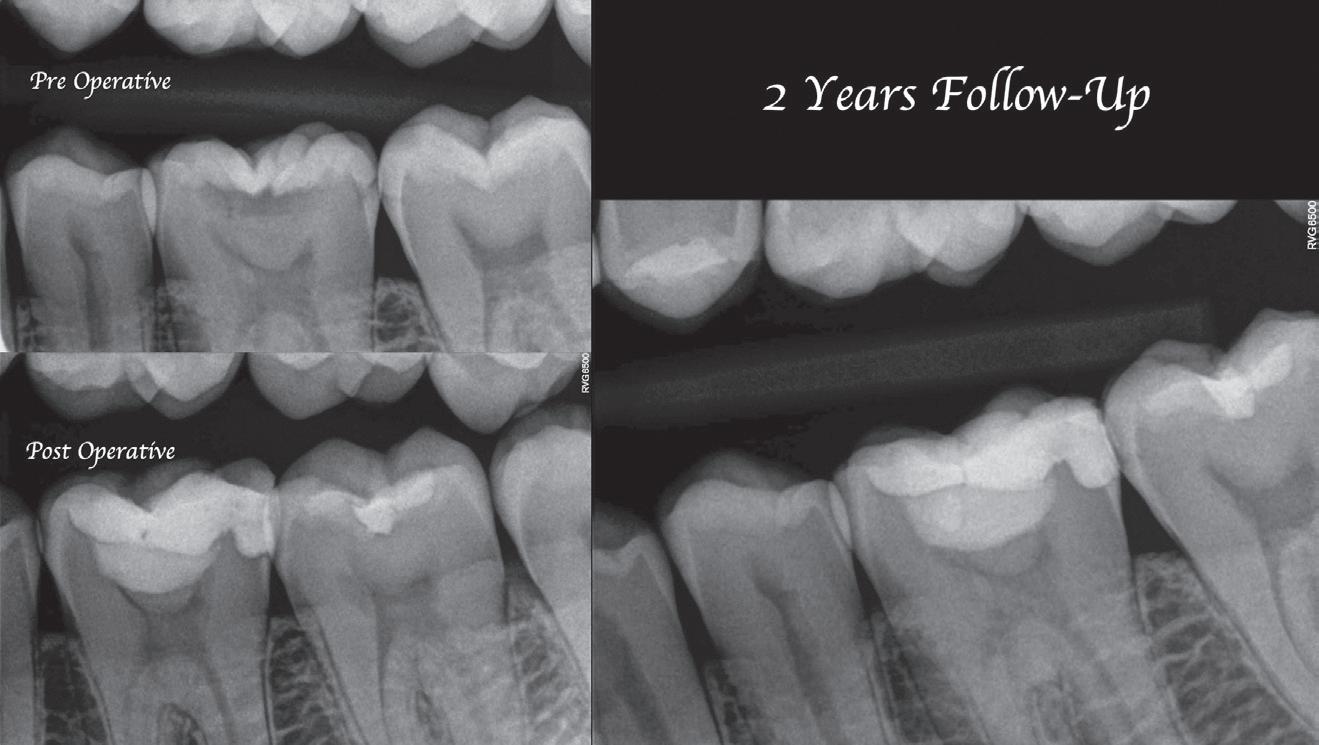

Clear radiographs are essential to accurate diagnosis and are a special test that dentists per form regularly many times throughout the day. Following the ALARA principle, we want to ensure we take a minimal number of radio graphs to ensure low radiation dosage so to repeat radiographs due to operator error should be avoided. The use of film holders allow the clinician to visualise how the radiographs should be taken to optimise the clarity of the image and ensure the diagnostic value of the image. Hawe Solutions x-ray film holders...

Figure 1: Radiographic Image of implants do not demonstrate bone loss due to the bisecting angle of the radiograph taken.

Figure 2: Radiographic image in a paralleling technique of implants dem onstrate moderate peri-implantitis with bone loss that will necessitate treatment.

• Allow exact posi tioning of the film or phosphor plate relative to the tooth - no bending and thus no distortion;

• Require no guesswork - exclusive, automatic reliance on the extraoral aiming and centring device;

• Deliver semi-reproducible images (quasi standardisation)the use of film holders allows some sense of reproducibility for assessment over time; and

• Produce optimally clear radiographs.